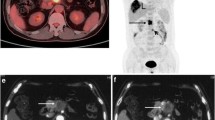

Contrast-enhanced CT and the first whole-body and delayed regional FDG PET/CT images of a 58-year-old male patient with rectal cancer. The contrast-enhanced CT images (a, b) show small low-attenuated lesions in the liver, left medial (0.5-cm-sized) and lateral (0.8-cm-sized) segments, suspicious of hepatic metastatic lesions. The first whole-body FDG PET (c) and fused PET/CT (d) images showed a focal hypermetabolic lesion in the left medial segment with a maximum SUV of 7.11 and tumor-to-liver (T/L) uptake ratio of 3.32, suggesting a metastatic lesion; however, no definite abnormal hypermetabolic lesion is seen in the left lateral segment. In the delayed regional liver PET (e) and fused PET/CT (f) images, two foci of hypermetabolic lesions are observed in the liver: medial segment (maximum SUV: 7.94, TLR: 3.91) and lateral segment (maximum SUV: 5.52, TLR: 2.72). These two lesions were histopathologically diagnosed as metastatic lesions from rectal cancer.